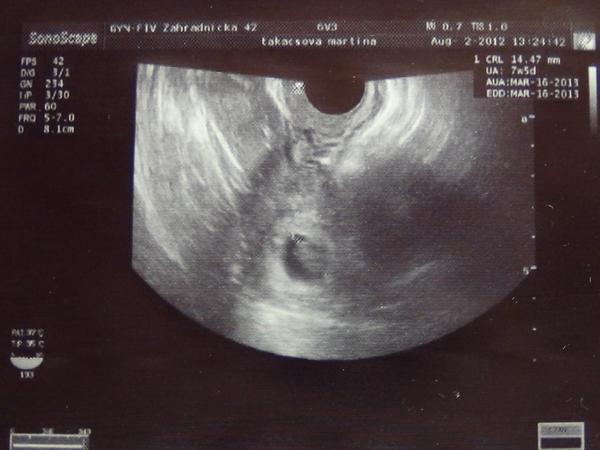

Ahojte babulky. Podelím sa s vami o túto krásnu fotku. Sme 7+5 tt, takže za chvíľu začíname 9tt. Dr hovoril, že je všetko v poriadku. Srdiečko krásne bilo 😵

@sheronka moc krásný, ani netušíš, jak je to pro mě povzbuzující. 😉 😉

@saraha2 já mu zatím věřím, i když holčina,co to měla podobně, mi napsala,že se diví,že mi v caru řekli,že mám brát dál prášky, jí zrovna řekli,že má vysadit - měla 49 a podruhé 51. No vidíš a zrovna @sheronka měla 32 a díííívej. 😀 😀 😀 (nespletla jsem to, byla jsi to Ty? 😀 )

@martina_81 Áno áno bola som to ja 😀 Bublinky sú bojovníci 😵

@sheronka jee to je nadhera!

@martina_81 taky budes mit za mesic takovou peknou fotecku !

@sheronka To je krásná fotečka hned po testíku s // šup do alba.Manža jistě ocení,byl s váma,nebo pracuje?Tak to si musíte s drobečkem koupit nějakou maličkost pro radost a třeba na památku 😉 Moc blahopřeju.

@sheronka krásná fotečka, MOC gratuluju 😵